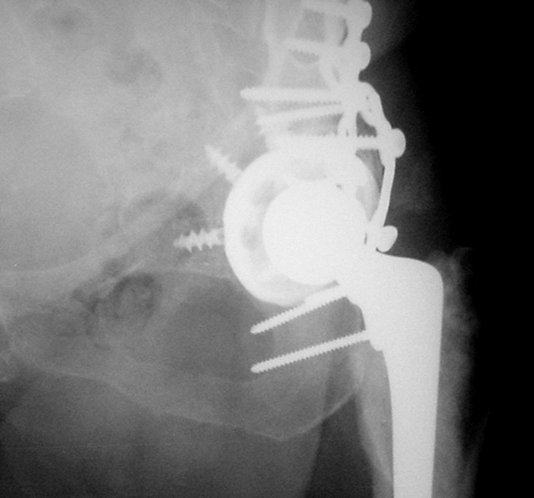

Обратились коллеги из городской больницы N36. Женщине 39 лет по поводу диспластического коксартроза около года назад выполнено эндопротезирование правого тазобедренного сустава. Вчера ехала на госпитализацию на протезирование второго сустава, и попала в аварию.

Получила поперечный перелом правой вертлужной впадины (снимок прилагается) с переломом ветвей лонной кости на другой стороне (inletview также в приложении), а также поперечный перелом дистального метафиза бедра на этой же стороне. Что посоветуете в отношении протеза и впадины? Спасибо заранее.

Ножка Алтимед, а чашка цементая???? Хороший гибрид. Насколько позволяет рентгенограмма, можно судить, что чашка стабильна (за счет цемента и арматуры в виде винтов). Нужен постельный режим не менее 6 недель.

Ситуация редкая и нестандартная. Складывается впечатление, что эндопротез вертлужной впадины стабилен. Я бы выполнил остеосинтез перелома в/впадины реконструктивной пластиной. Эти переломы срастаются хорошо.

Установлена RM-чашка бесцементная,ножка тип Цвайммюллер производства Мathys,сделана костная пластика.В настоящее время необходим остеосинтез реконструктивной пластиной без удаления чашки,так как чашка стабильна.